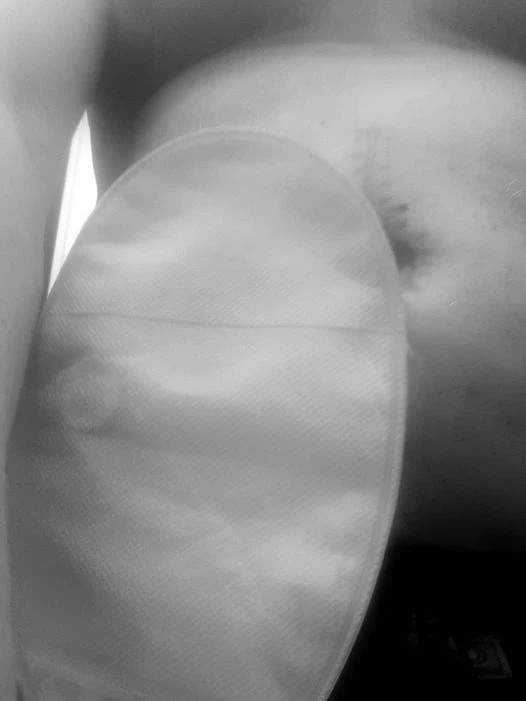

Så såg min mage ut dan innan operation: Och påsen hamnade på Högra sidan på pricken de ritade: 2024-02-27

Så ser de ut med min påse på magen.. Men Idag har jag mindre platta, och ser mer av ärret.... & allt går lätt att byta och så!!